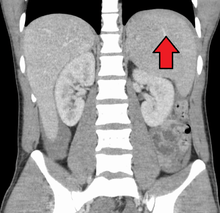

Spleen enlargement is common in the second and third weeks, although this may not be apparent on physical examination. Rarely the spleen may rupture. There may also be some enlargement of the liver.[20] Jaundice occurs only occasionally.[12][21]

A few studies on infectious mononucleosis have been conducted in a primary care environment, the best of which studied 700 patients, of which 15 were found to have mononucleosis upon a heterophile antibody test. More useful in a diagnostic sense are the signs and symptoms themselves. The presence of an enlarged spleen, and swollen posterior cervical, axillary, and inguinal lymph nodes are the most useful to suspect a diagnosis of infectious mononucleosis. On the other hand, the absence of swollen cervical lymph nodes and fatigue are the most useful to dismiss the idea of infectious mononucleosis as the correct diagnosis. The insensitivity of the physical examination in detecting an enlarged spleen means it should not be used as evidence against infectious mononucleosis.[20]

Splenomegaly is a common symptom of infectious mononucleosis and health care providers may consider using abdominal ultrasonography to get insight into the enlargement of a person's spleen.[50] However, because spleen size varies greatly, ultrasonography is not a valid technique for assessing spleen enlargement and should not be used in typical circumstances or to make routine decisions about fitness for playing sports.[50]